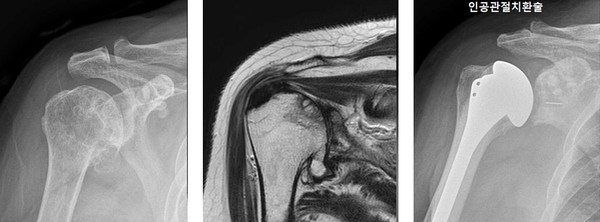

어깨 관절염 치료는 환자 상태에 따라 달라진다. 성창훈 대표원장은 "초기에는 약물치료, 물리치료, 보조기 착용 등의 비수술 치료법으로 회복할 수 있지만 비수술 치료로도 호전되지 않고 힘줄 파열로 마비 증상이 나타나거나 관절염 말기일 경우에는 인고관절치환술 등의 어깨 수술을 반드시 검토해야 한다"고 설명했다.